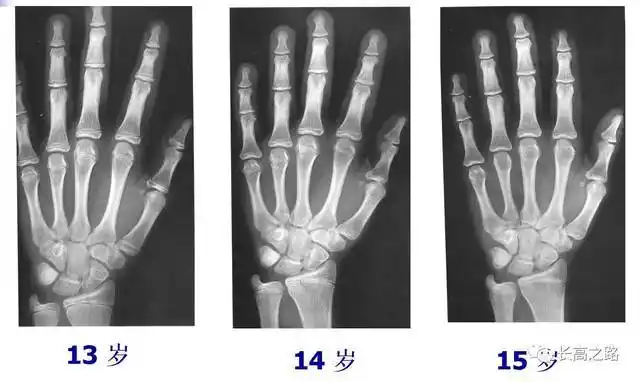

临床医学表明,人一旦骨骺线闭合,无论任何方法,都不可能再长高.

长高#看身高要尽早,骨骺线完全闭合,就没翻盘机会了